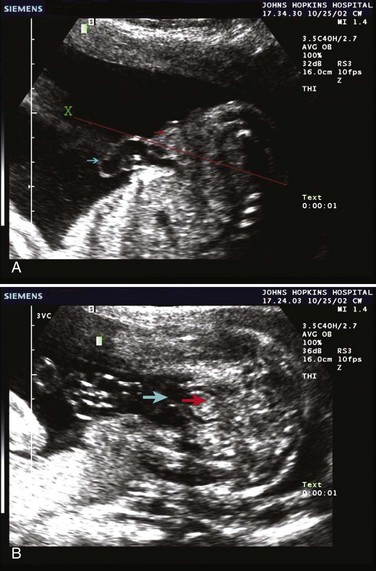

Currently, the prenatal diagnosis of bladder exstrophy is difficult to delineate. Often, a diagnosis of omphalocele or gastroschisis is made and the exstrophy condition is overlooked. Ultrasound evaluation of the fetus, by means of high-resolution real-time units, allows a thorough survey of the fetal anatomy, even during routine obstetric ultrasound examinations (Gearhart et al, 1995a). Several groups have outlined important criteria for the diagnosis of classic bladder exstrophy prenatally. In these reviews, the absence of a normal fluid-filled bladder on repeated examinations suggested the diagnosis, as did a mass of echogenic tissue on the lower abdominal wall (Mirk et al, 1986; Verco et al, 1986). In a review of 25 prenatal ultrasound examinations with the subsequent birth of a newborn with classic bladder exstrophy (Gearhart et al, 1995a), several observations were made: (1) absence of bladder filling, (2) a low-set umbilicus, (3) widening pubis ramus, (4) diminutive genitalia, and (5) a lower abdominal mass that increases in size as the pregnancy progresses and as the intra-abdominal viscera increases in size (Fig. 124–15).

Figure 124–15 Prenatal ultrasound scan demonstrating bladder exstrophy. A, Longitudinal view showing the low-set umbilicus (cyan arrow), lack of intra-abdominal bladder, and lower abdominal mass (red arrow). B, Transverse view through the plane (X) in A shows presence of the umbilicus (cyan arrow) and the upper edge of the bladder plate that appears hyperechoic (red arrow).